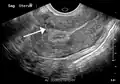

A very large (9 cm) fibroid of the uterus which is causing pelvic congestion syndrome as seen on ultrasound